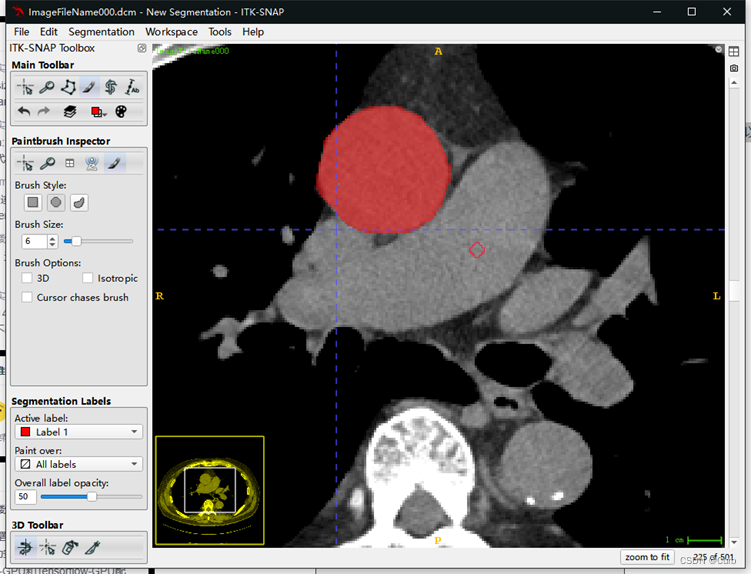

标注方法二:画笔标注

这里只进行简单介绍,流程和上面的套索标注差不多

在这一功能中可以使用类似画笔工具对标注的mask进行修改,在这个功能下鼠标左键是画笔,鼠标右键是橡皮。可以通过brush style和brush size调整笔头的形状和大小。